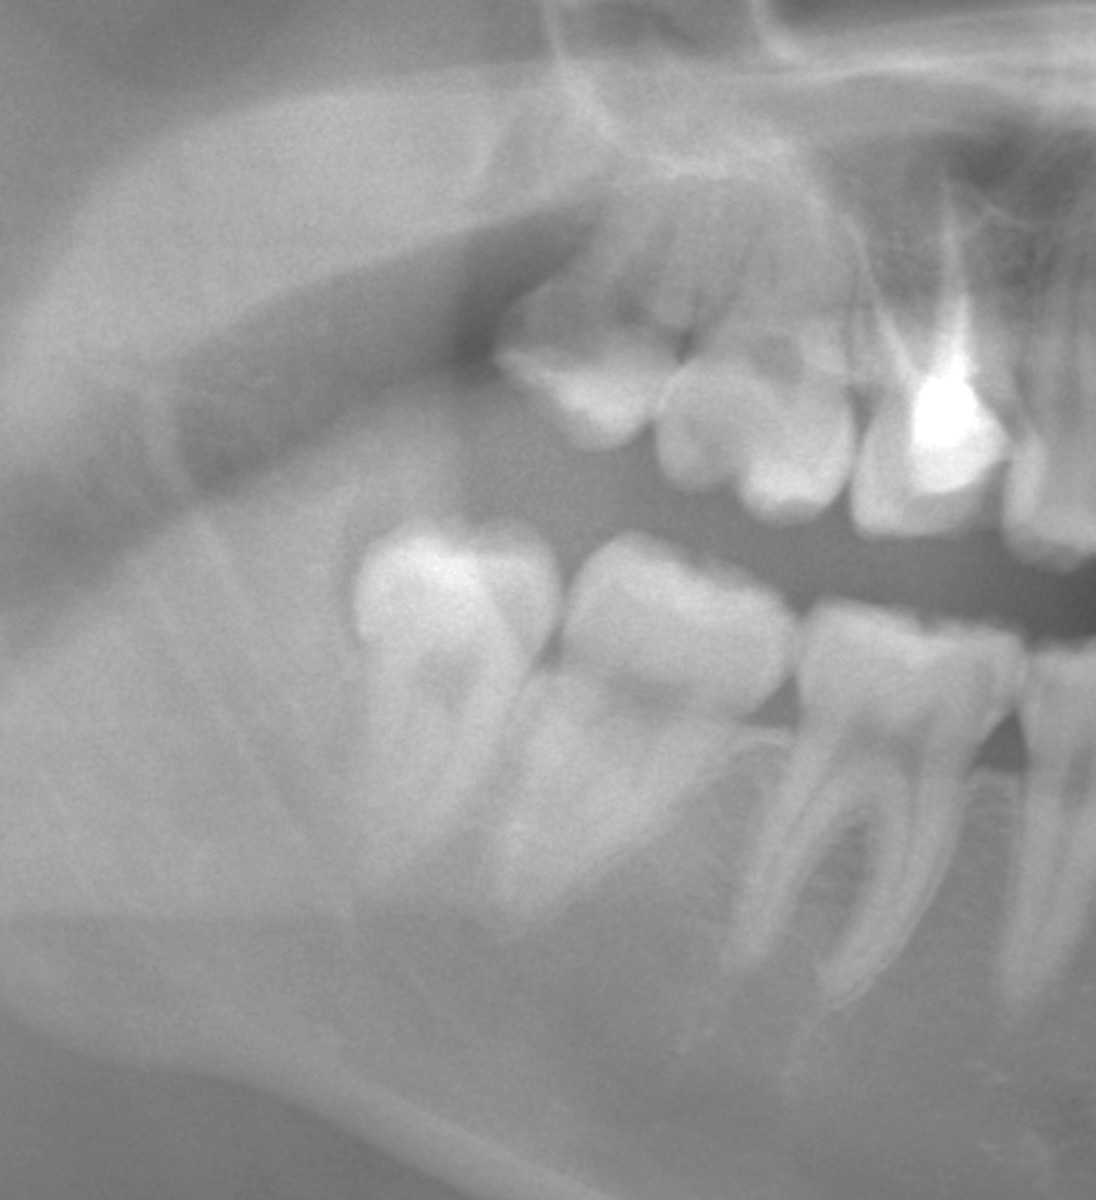

20代の女性が、他院からの紹介で「下顎の親知らず抜歯」を目的に当院を受診されました。

* 右下親知らず:垂直に生えているものの、歯の後ろ側(遠心歯冠部)が骨に覆われている状態

* 左下親知らず:水平に完全埋伏し、下歯槽神経に近接

どちらも抜歯が必要なケースでした。特に左下は難易度が高く、紹介で来院される方が多い典型的な症例です。